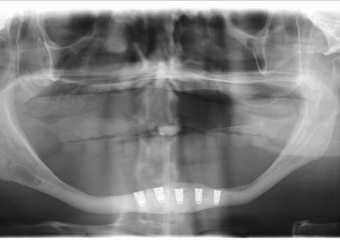

Raio - x Panorâmico Implantes inferiores instalados, em Outubro de 2015